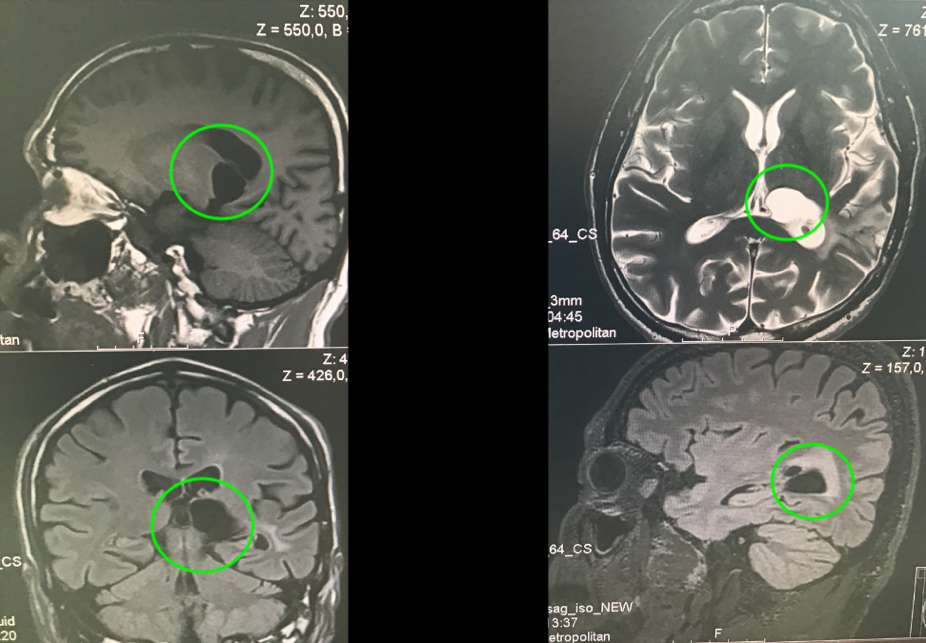

在5-ALA荧光、术中神经导航和术中MRI辅助手术,通过左侧顶枕枕骨开颅术和显微外科肿瘤全切手术,手术顺利,无手术并发症。

术中磁共振检查,显示肿瘤准确全切

(红色表示切除前,绿色表示切除后)